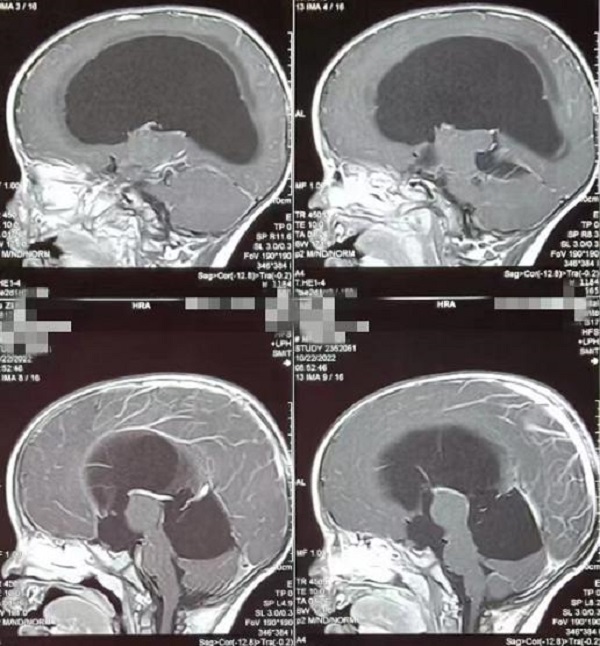

一岁多的赫赫小朋友自出生头颅就比同龄小孩大,近半月来进食后出现呕吐,伴头痛,在当地医院及省内多家医院治疗不见好转,于是来到二一五医院神经重症监护室,因患儿近半月多不能正常进食,入院时精神萎靡,头颅MRI检查提示“脑室系统扩大,双侧脑室额角周围间质水肿,左侧丘脑占位病变,鞍上池及小脑上池扩大”。

为进一步鉴别脑积水类型,行磁共振3D FIESTA序列检查可见侧脑室扩大明显,中脑导水管中段阻塞、三脑室底受压下陷,诊断梗阻性脑积水。